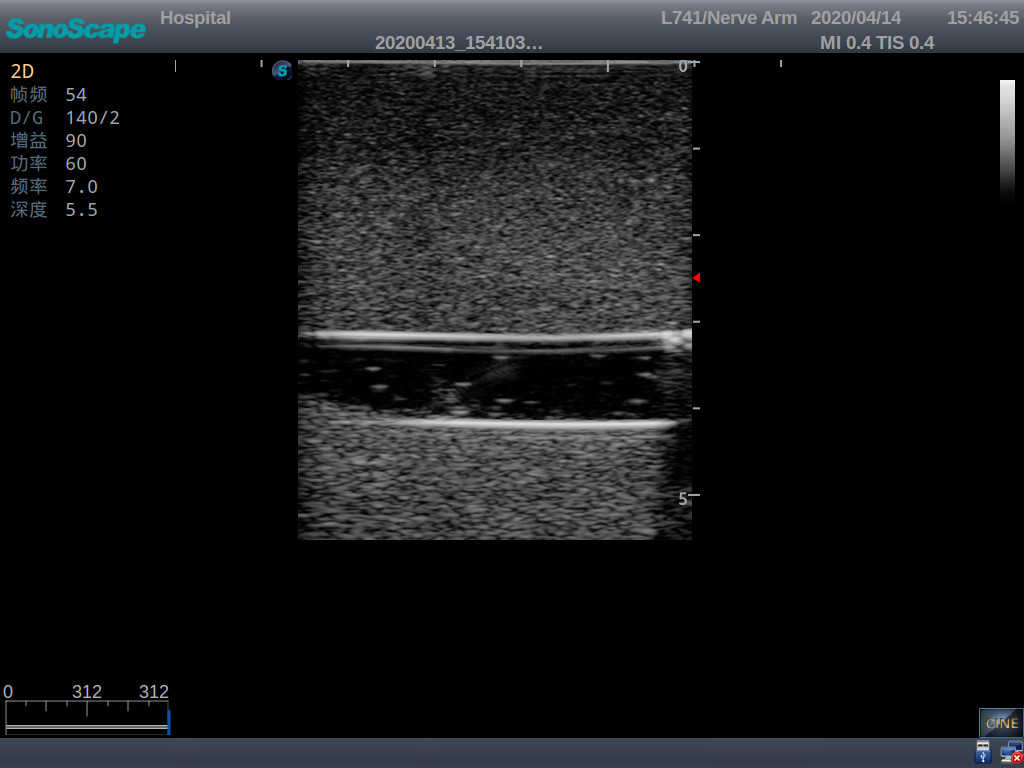

2) It can be used by real ultrasound machines

3) Clear and real images of the tissues and organs (basilic vein and superior vena cava)

5) Observe the guide wire marches

6) Detect whether the catheter is properly placed